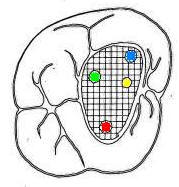

Cuarto conducto en molares superiores (Color amarillo conducto mesio-palatino)

Primer molar superior

La raíz mesiovestibular es achatada en sentido mesiodistal y amplia en sentido vestibulopalatino.El conducto mesiovestibular con frecuencia es curvo y de sección en forma de hendidura. La existencia de dos conductos en esta raíz, puede presentar la siguiente configuración:

• uno vestibular (Color azul)

• y el otro palatino (Color amarillo)

Estos conductos pueden unirse a distintos niveles, terminando en un foramen único o ser de trayectoria independiente hasta el ápice y terminar en forámenes separados. Son atrésicos y de difícil tratamiento en especial el palatino.

La raíz distovestibular tiene dimensiones menores que la mesiovestibular y no presenta curvaturas acentuadas. El conducto distovestibular (Color verde) por lo general es atrésico y puede presentar curvaturas.

La raíz palatina es la más voluminosa de forma cónica y sección circular. Puede ser recta o curva. Cuando es curva, el sentido e la curva es hacia vestibular. El conducto palatino (Color rojo) es amplio y de fácil acceso, rectilíneo o con una curva leve hacia vestibular.